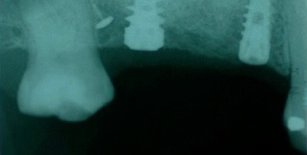

Grande rialzo del seno mascellare

Perdita di elementi dentari postero-superiori di destra, con assenza di osso per poter posizionare impianti osteo-integrati.

Si rigenera l'osso necessario attraverso l'intervento di GRANDE RIALZO DEL SENO MASCELLARE.

A rigenerazione ossea stabilizzata si procede all'inserzione degli impianti e alle fasi protesiche definitive.